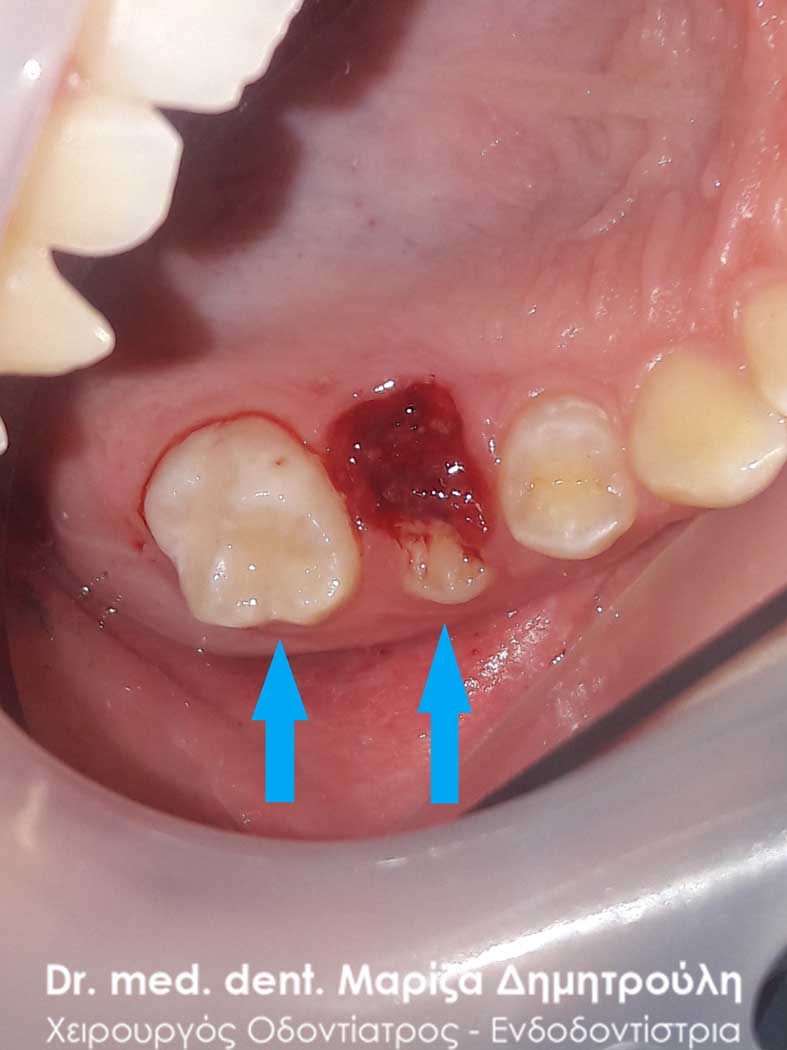

AFTER